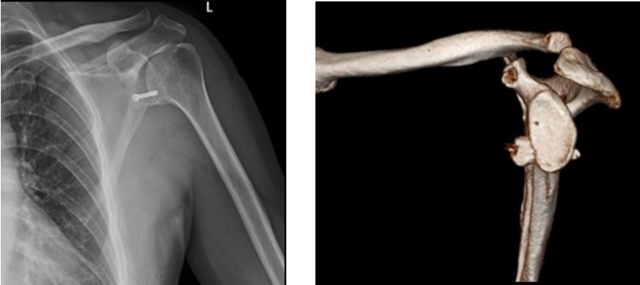

经详细检查,小刘被诊断为盂唇撕脱损伤严重,肩关节囊变得松弛,肱骨头后上方有较大骨缺损,属于习惯性肩关节脱位,体征明显、症状严重。

对小刘的病情进行充分评估后,大骨科主任兼骨伤科关节·足踝组主任扶世杰教授和暴丁溯决定为他实施全关节镜下肩关节前向不稳修复术。

术中,医生截断了患者喙突,进行了骨块的移植螺钉固定,填补关节盂的缺损,起到了阻挡肱骨头的作用,避免了肩关节再次脱位。